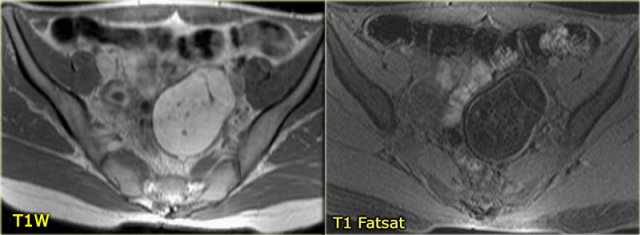

Hemorrhagic ovarian cyst Hemorrhagic ovarian cyst

On an axial T1-weighted image both lesions are bright indicating fat, blood or high protein fluid.

Fat saturation does not suppress the signal in these lesions.

In an image with overall reasonably good fat suppression this rules out a fat-containing teratoma and confirms the suggestion of hemorrhagic fluid.